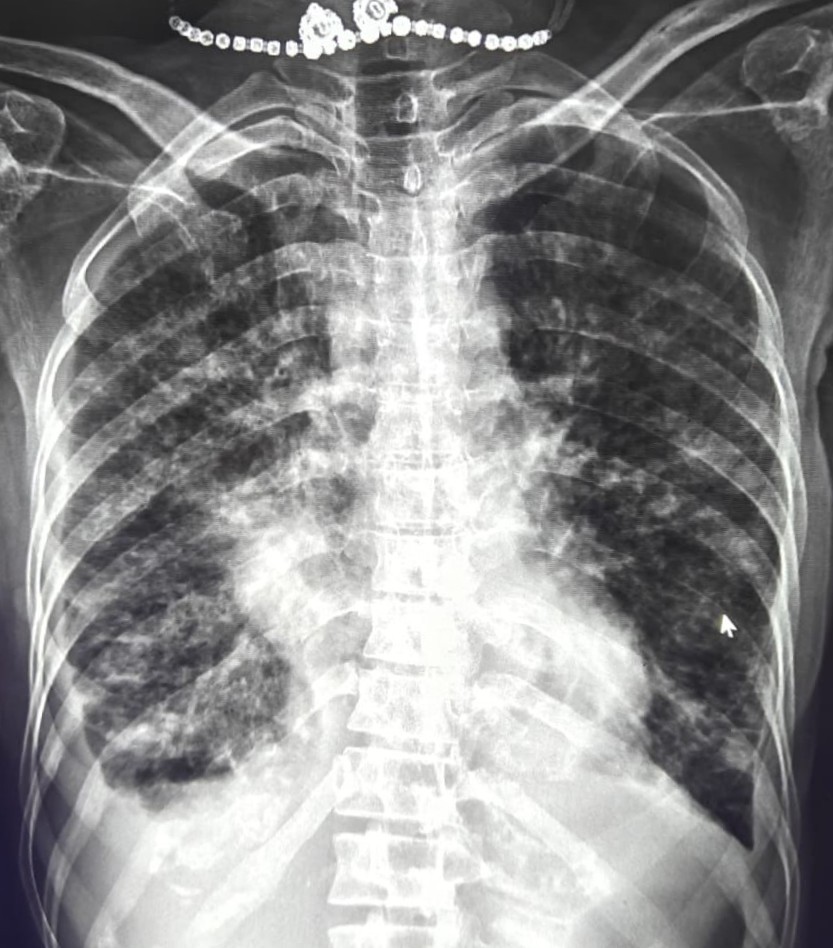

| 209 | IGGMC, Nagpur, Nagpur | P2 | 29-4263 | MONIKA KAITHAL | Consent taken on Paper | 47 Yrs. |

Provisional Diag : B/L LUNG CONSOLIDATION PNEUMONIA?

Final Diag : B/L CONSOLIDATION/PNEUMONIA |

TB Case (Confirmed) | B/L LUNG CONSOLIDATION | Abnormality visible on x-ray |

View |

|||